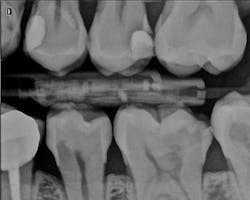

The patient, a 29-year-old man, presented with a failing Class II direct composite restoration in the upper left second premolar (figure 2). A radiograph confirmed the presence of a carious lesion (figure 3). Due to the recurrent caries found in many of the teeth, a conservative treatment plan was made for possible root canal therapy and a direct composite restoration. In cases with recurrent caries, using an RMGI is ideal in that it contains fluoride and provides a more suitable "environment" for restoring deep lesions.

Figure 2: A failing Class II direct composite restoration in the upper left second premolar

Figure 3: Radiograph confirming carious lesion